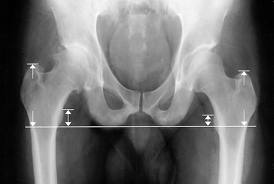

Hansen and colleagues performed a retrospective study of 170 patients who underwent primary total hip replacement (THR). The investigators excluded patients from the study who displayed abnormal anatomy or a had a body mass index of more than 46, as well as those who underwent simultaneous removal of internal fixation and those who had incomplete data. Leg length was measured by assessing the inter teardrop line and lesser trochanter on radiographs.

However, they found a significant difference in the proportion of patients who displayed a leg length difference of more than 7 mm — 22% in the spinal anesthesia group and 6% in the TIVA group. They also noted average total time spent in the theater and recovery room was significantly higher in the spinal group than in the TIVA group.